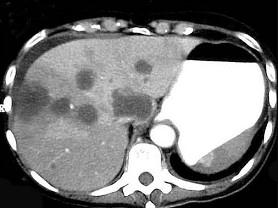

问题 继发性肝癌诊断的关键是 ( )

选项 A、行CT检查 B、测定血清甲胎蛋白 C、行肝动脉造影检查 D、行放射核素扫描 E、查清原发癌灶 单选题

答案 E